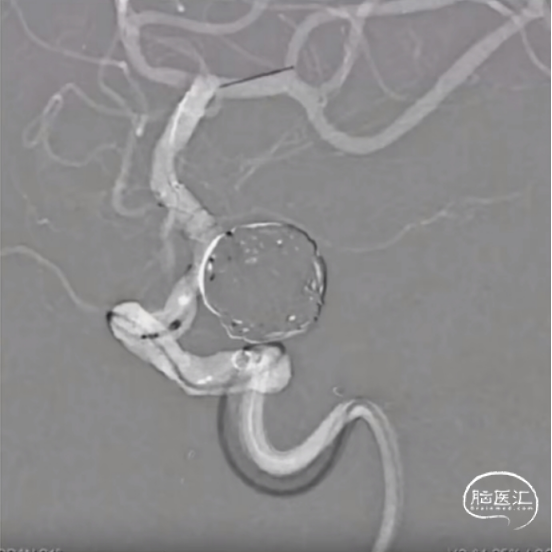

经测量可得动脉瘤宽度平均值为7.0mm,动脉瘤高度为5.18mm,选用WEB™ SL 8*4。

WEB™经由VIA™微导管送入动脉瘤瘤腔并完全释放。术后即刻造影显示WEB™尺寸合适,贴壁良好,分支等血流通畅。解脱后再次造影,可见动脉瘤瘤腔内有明显造影剂滞留。

术后3个月随访,WEB™完全栓塞,动脉瘤完全闭塞。